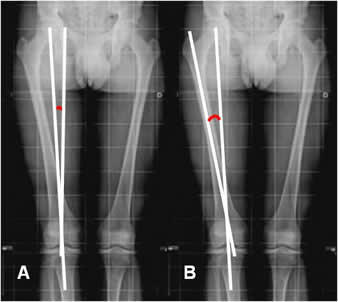

Fig 98 A. Genu valgo de origen femoral.

Eje desplazado lateralmente y líneas tangenciales paralelas.

Fig 98 B. Genu valgo de origen tibial.

Eje desplazado lateralmente y líneas tangenciales con ángulo de vértice lateral.

Fig 98 C. Genu varo de origen femoral.

Eje desplazado medialmente y líneas tangenciales paralelas.

Fig 98 D. Genu varo de origen tibial.

Eje desplazado medialmente y líneas tangenciales con ángulo de vértice medial.